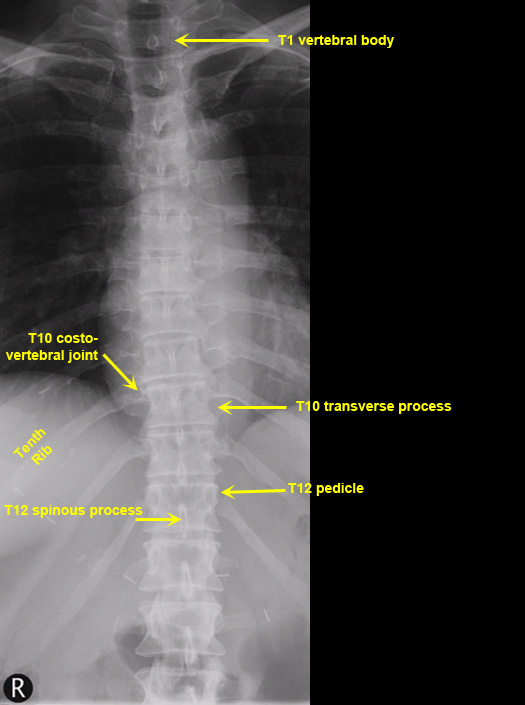

Plain Films of Skull and Spine